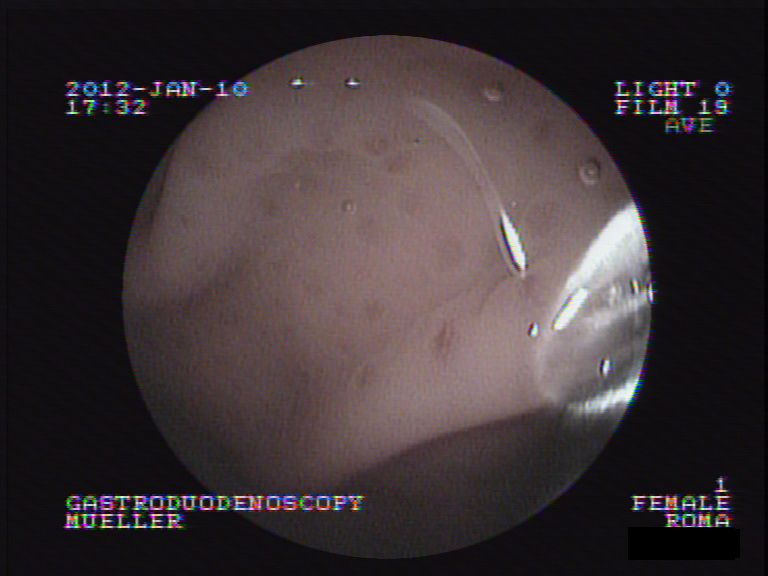

Nun wird als letzter Schritt das Problemorgan Magen direkt inspiziert. Unter Narkose wird eine Magenspiegelung durchgeführt - über die digitale Optik kann so die Magen- und Darmschleimhaut begutachtet werden.

Bei Roma zeigt sich, dass die Magenschleimhaut über weite Strecken glasig-weisslich erscheint. Sie enthält aber keine Blutungen, auch scheint der Magenausgang normal durchgängig und die Darmschleimhaut des oberen Dünndarms scheint normal. Durch einen Arbeitskanal im Endoskop werden mittels einer Biopsiezange mehrere Gewebeproben der Schleimhaut entnommen und in einem externen Labor untersucht.